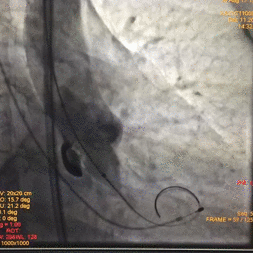

术中影像

图片

根部造影

球囊预扩

瓣膜释放至2/3造影观察

瓣膜释放后形态欠佳

经球囊后扩后瓣膜形态良好

手术结果

术后造影及超声探查未见瓣周漏,跨瓣压差术前183mmHg,术后几乎无压差,术中及术后未出现相关并发症,手术圆满完成。